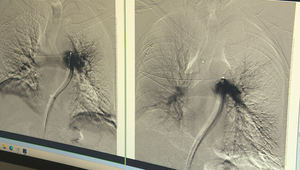

Sekundy rozhodujú. Lekári zachraňujú pacientov s pľúcnou embóliou unikátnym zákrokom